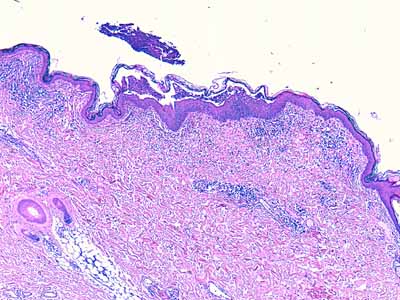

A l’examen histologique, on observe des pustules intra-épidermiques, sous-cornées, planes, extensives, pontant l’abouchement de plusieurs follicules pileux voisins (Photo 1,2) et pouvant contenir des cellules épithéliales acantholytiques (Photo 10,11,12,13). Leur plancher épidermique montre une forte exocytose éosinophilique (Photo 10,11,12,13). Le derme est le siège d’un infiltrat inflammatoire de topographie périvasculaire (Photo 8,9), riche en macrophages, granulocytes éosinophiles et plasmocytes. Certains macrophages contiennent dans leur cytoplasme un élément rond à ovalaire, bi-polaire de quelques micromètres de diamètre, dont la silhouette est fortement compatible avec un parasite protozoaire du genre Leishmania (Fig14).

Photo 8 (Hémalun Eosine X 40) : L’épiderme est parsemé de vésiculo-pustules sous-cornées,

extensives, planes, dont le toit, composé de fines lamelles de kératine orthokératosique, est fragile.

Le derme montre un infiltrat de topographie péri-vasculaire.

Le patron lésionnel est celui d’une dermatite psutuleuse sous-cornée périvasculaire.

Légendes de la Photo 8 :

- Pointe de flèche turquoise : pustule intra-épidermique sous-cornée

- Flèche orange : infiltrat dermique de topographie péri-vasculaire

- Étoiles rouges pleines : vaisseaux sanguins

- Étoiles rouges vides : follicules pileux

Photo 9 (Hémalun Eosine X 40) : Les pustules sous-cornées qui parsèment l’épiderme,

peuvent ponter l’abouchement de plusieurs follicules pileux voisins.

Légendes de la Photo 9 :

- Double flèche noire : épiderme

- Double flèche pointillée noire : derme

- Pointes de flèche turquoise : délimitation de la pustule intra-épidermique sous-cornée qui ponte l’abouchement de trois unités folliculo-sébacées

- Pointes de flèche jaune : toit rompu de la pustule (fines lamelles de kératine orthokératosique)

- Cercles marrons : glandes sébacées

- Étoiles rouges pleines : vaisseaux sanguins

- Étoiles rouges vides : follicules pileux

- Étoiles turquoises : glandes sudorales apocrines épitrichiales

- Flèche orange : infiltrat dermique de topographie péri-vasculaire